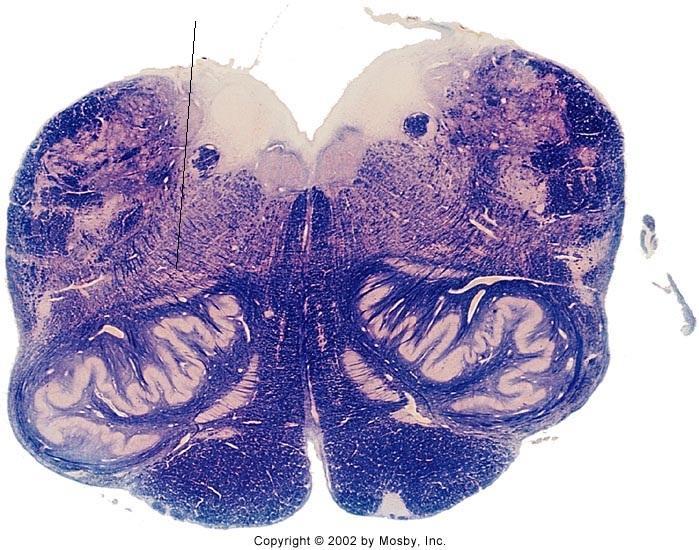

What section of the brainstem does this image come from?

caudal pons